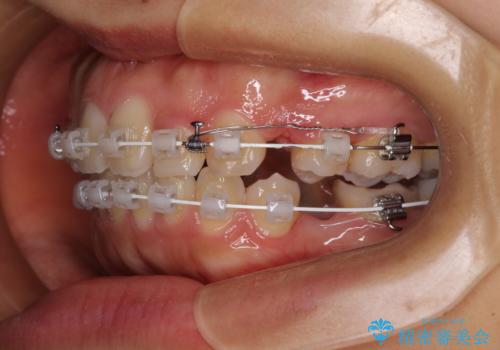

- 審美装置

- 2年2ヶ月

- 10-30回

上顎抜歯のみでは奥歯の咬み合わせを改善することが困難であったため、途中で下顎小臼歯も抜歯をしました。

抜歯のタイミングが遅れると治療期間が長期化するため、速やかに抜歯の判断をし、2年強の期間で治療を終えることができました。